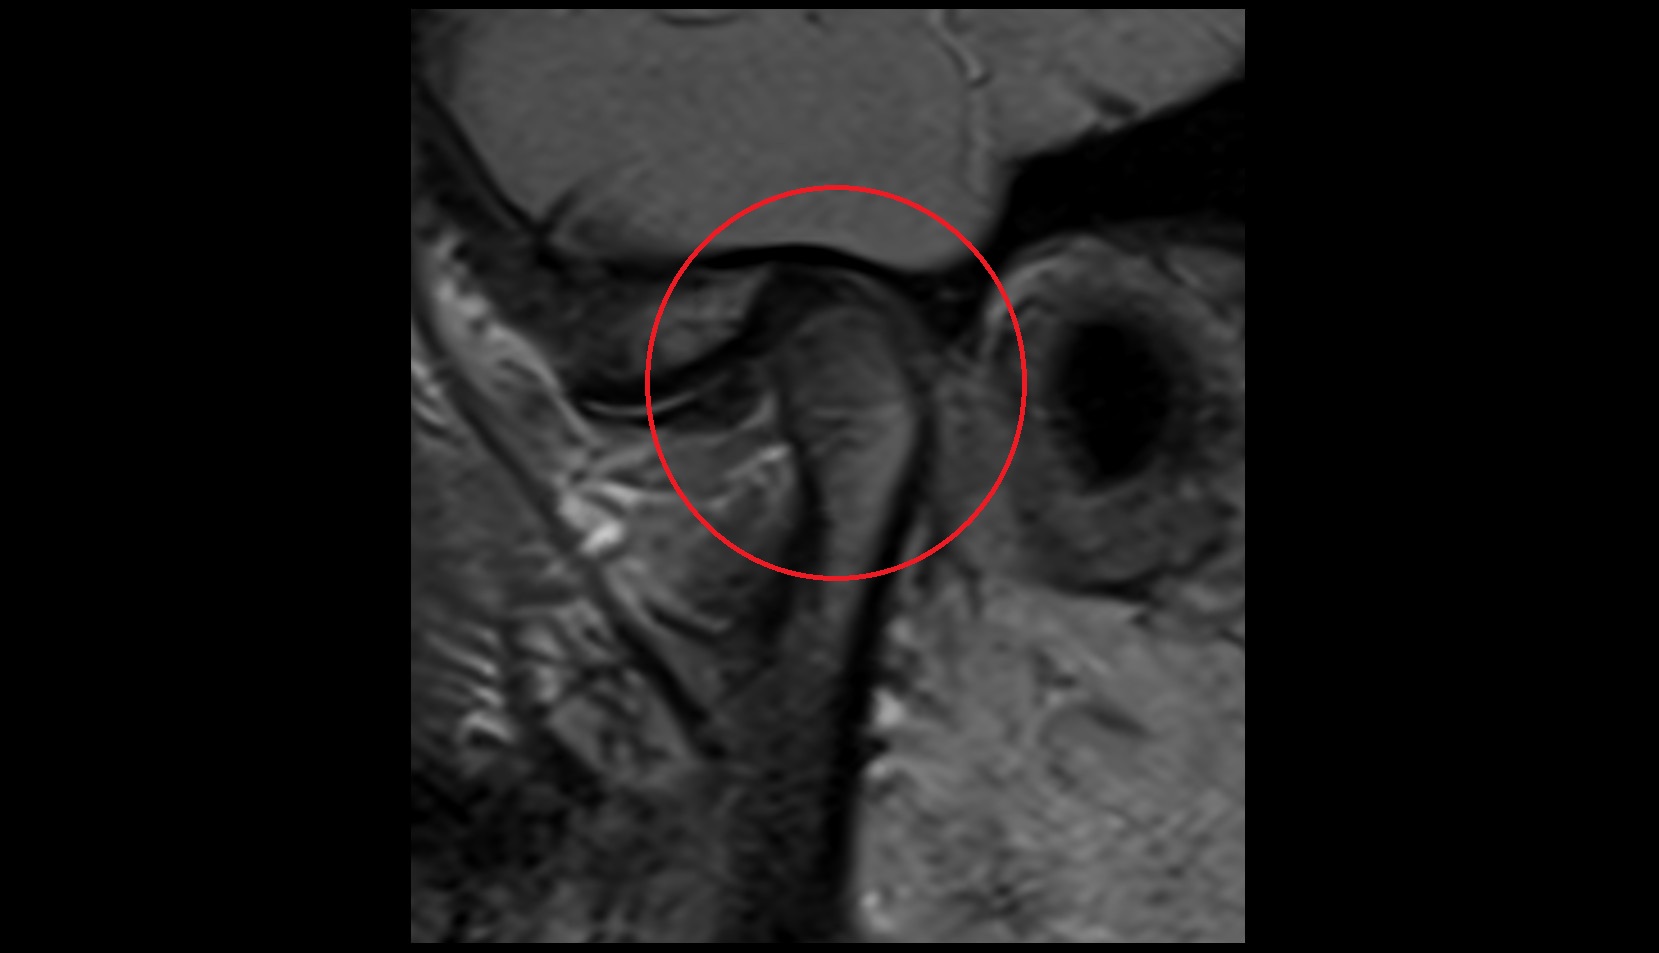

- Anterior Band of Articular Disc TMJ

- Posterior band of articular disc, TMJ

- Articular disc of temporomandibular joint

- Intermediate zone of articular disc

- Superior retrodiscal layer